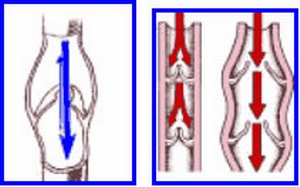

根據調查統計, 約有百分之25的女性, 和百分之18的男性, 罹患嚴重程度不等的靜脈曲張(varicose vein, vein reflux), 屬於慢性的文明病. 靜脈一般而言分成三種; 第一種乃深層靜脈(deep veins), 位於肌肉和纖維組織之間, 負責的靜脈血(也就是缺氧血, deoxygenated blood)的回流至心臟; 第二種是表淺靜脈(superficial veins), 位置在皮膚表層, 功能在收集表淺的血液; 第三種是穿透靜脈(perforator veins), 乃連接前兩種靜脈, 負責把表淺靜脈的血液帶到深層靜脈裏. 它的功能主要是把缺氧血帶回心臟

也就是把用過的血液, 攜帶廢物的血, 像下水道, 收集至心臟重新改造, 以利重新運用. 不料靜脈裡面, 控制血液回流方向的瓣膜(VALVE), 在靜脈曲張的患者是受損的, 所以靜脈血亂流一通, 甚至蓄積或賴在遠方不回去, 使得靜脈水袋越撐越大 越歪七扭八, 久了就變形了! 俗稱「浮腳筋」!